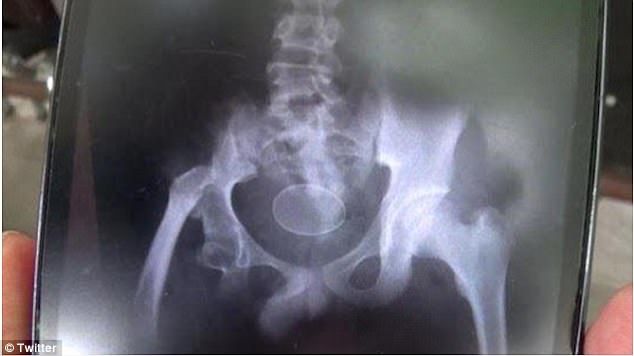

インドネシアの南スラウェシ州に住む少年、Akmal君(14)が鶏卵を産んだとして医師を困惑させている。

少年はこの2年で合計20個の卵を産み落としてきた。

そう話すのは、14歳になったAkmal君。父親のRusliさんが実際に肛門から排出された”異物”を割ってみたところ、紛れもなく本物の卵だったようだ。

”産卵”のたびに病院へ行くが、前代未聞の事態に医師たちも頭を抱えてしまっている。

「息子は今日は医師たちの前で2個の卵を産んだのです。これで20個ですね。最初の卵を割ってみましたが、中身は卵白がなく、すべて卵黄でした」